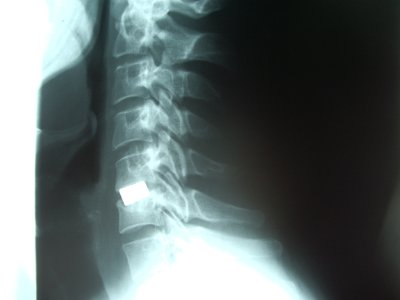

Columna cervical